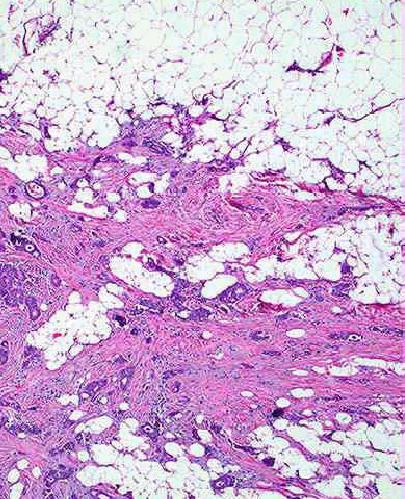

Một số hình ảnh giải phẫu bệnh lý của u biểu mô tuyến vú:

H4: Ung thư biểu mô ống xâm nhập biệt hóa rõ